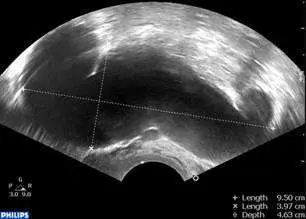

本題圖片為**陰道超音波(transvaginal ultrasound)**影像,使用 PHILIPS 機器拍攝。

- 影像中可見一個位於子宮附屬物區域的長橢圓形、管狀無回聲(anechoic)液性囊狀結構,外觀呈香腸形(sausage-shaped)

- 影像右側標示測量數值:

- Length(最長徑):9.50 cm

- X Length(橫徑):3.97 cm

- Depth(深度):4.63 cm

- 囊狀物內部為均勻無回聲,符合液性內容物

- 結構邊界清楚,呈管狀延伸

臨床意義: 這種「香腸般」(sausage-shaped)的管狀液性囊腫是 hydrosalpinx 的病理徵象(pathognomonic)。最長徑 9.5 公分、最寬 3.9 公分的尺寸與題目描述完全吻合,且位於子宮附屬物區域(而非子宮